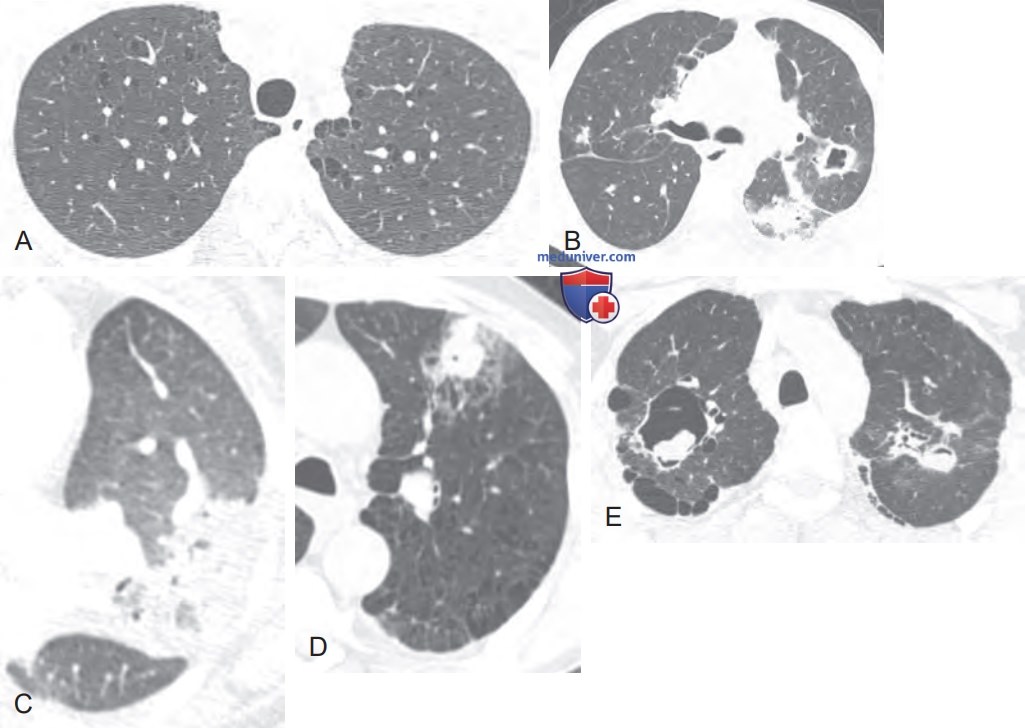

Кт признаки эмфиземы